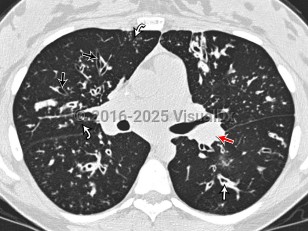

Cystic fibrosis is a congenital metabolic disorder caused by a mutation in a protein that regulates chloride ion transport. This leads to viscous secretions and eventual dysfunction of exocrine glands, most notably affecting the lungs and pancreas. Symptoms usually appear in childhood and include recurrent pulmonary infections with gradual loss of pulmonary function and pancreatic insufficiency leading to poor weight gain. Liver involvement can range from steatosis to advanced cirrhosis with portal hypertension.

Only about 4% of cystic fibrosis patients are diagnosed as adults. Adult patients may also develop pancreatic endocrine insufficiency and cystic fibrosis-related diabetes, which involves both insulin deficiency and resistance. Most adult cystic fibrosis patients will ultimately die of respiratory failure.

Pseudomonas aeruginosa, Staphylococcus aureus, and Mycobacterium abscessus infections are complications of cystic fibrosis. Patients with cystic fibrosis may be anemic. Patients often have impaired absorption in the small bowel and ciliary dysfunction in the genitourinary system that can impact fertility.